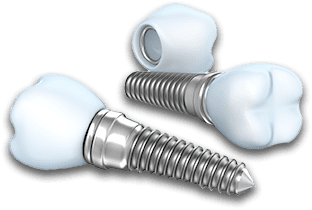

インプラントとは何ですか?歯科用インプラントとは、チタンでできた人工歯根のことです。インプラント治療では、このインプラントを顎の骨に埋め込み、先端に人工歯を装着することで歯を補います。入れ歯よりも自然に近い咬み心地が得られます。

インプラント体を埋入し、ネジの部分に仮の蓋を着けます。手術前はしっかりと消毒を行い、器具もすべて滅菌します。麻酔もしますので、手術中の痛みはあまりありませんが、麻酔が切れると手術後に痛みが出ることもあります。お薬が出ますので、処方通りに飲んで下さい。また、手術後は消毒にお越し下さい。

被せ物が出来上がったら装着し、噛み合わせを調整します。緊密に調整することで、より長くインプラントをもたせることができます。